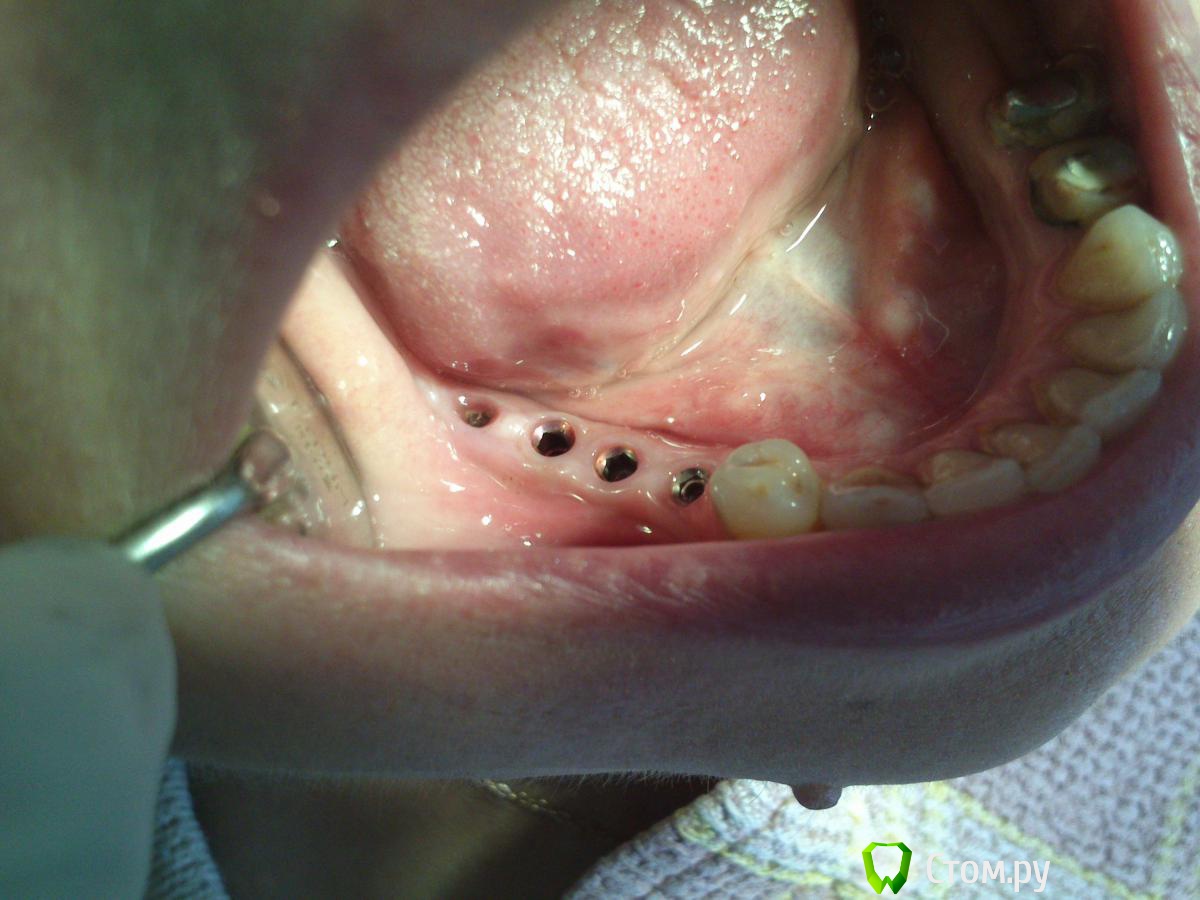

St_Klaus Опубликовано 1 октября, 2014 Поделиться Опубликовано 1 октября, 2014 Фото нет? Хочется на количество десны взглянуть. Ссылка на комментарий

GoDemon Опубликовано 1 октября, 2014 Автор Поделиться Опубликовано 1 октября, 2014 Фото нет? Хочется на количество десны взглянуть.Вот, сегодня специально попросил придти... 1 Ссылка на комментарий